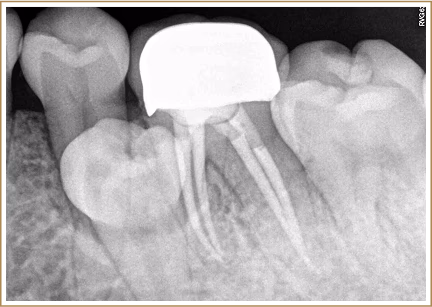

杜牙根後牙齒的剩餘結構較少,牙齒變得脆弱容易斷裂。

牙冠可以提供額外的保護,防止牙齒崩裂。

CAD/CAM技術製作的牙冠較傳統牙冠更密合,減低長期使用二次蛀牙、酸痛、異味發生率 👍🏻